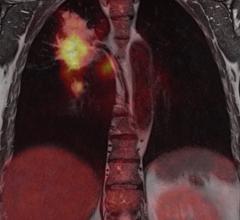

PET-CT combines positron emission tomography (PET) detectors and computed tomography (CT) into one imaging system.

Since entering the market in 2001, PET/CT (positron emission tomography/computed tomography) has come a long way in ...

Technological advancements in positron emission tomography/computed tomography (PET/CT) offer both clinicians and ...